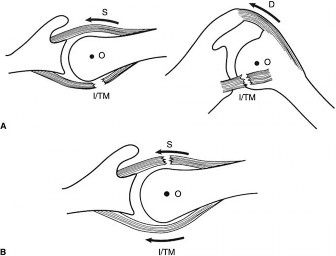

The correct answer is (D). One of the functions of the rotator cuff is to dynamically stabilize the humeral head in the glenoid, providing a fulcrum so that the shoulder can articulate properly. In order to do this, forces around the center of rotation must be equal in the transverse and coronal planes. In the transverse plane, the humeral

head is relatively unconstrained by the glenoid anteriorly and posteriorly. Any anterior and posterior forces placed on the humeral head must be balanced so that it does not sublux or dislocate in an anterior or posterior direction. This is accomplished by the subscapularis pulling the humeral head anteriorly with the same force that the infraspinatus and teres minor pull it posteriorly. All of these muscles also act to pull the humeral head medially into the concavity of the glenoid, stabilizing it in a medial-lateral dimension. When a patient has a rotator cuff tear, these force couples become uneven and can lead to instability (see Fig. 2–7).

Figure 2–7A. The transverse plane force couple (left) and the coronal plane force couple (right) are disrupted by a massive rotator cuff tear involving the posterior rotator cuff, infraspinatus, and teres minor. B. An alternative pattern of disruption of the transverse plane force couple. The transverse plane force couple is disrupted by a massive tear involving the anterior rotator cuff (ie, subscapularis). D = deltoid, I = infraspinatus, O = center of rotation, S = subscapularis, TM = teres minor. (From Burkhart SS, Lo IKY. Arthroscopic rotator cuff repair. J Am Acad Orthop Surg. 2006;14(6):333–346.)